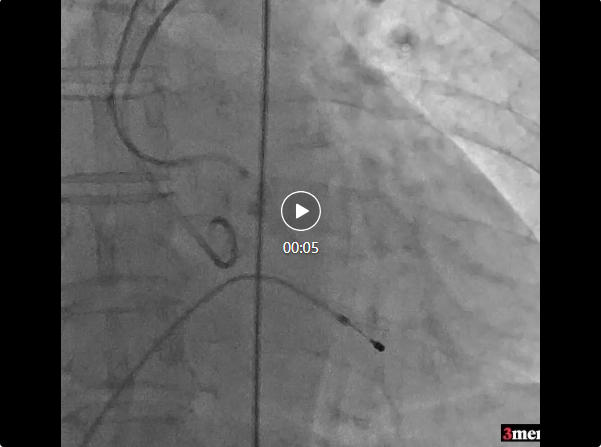

瓣膜釋放